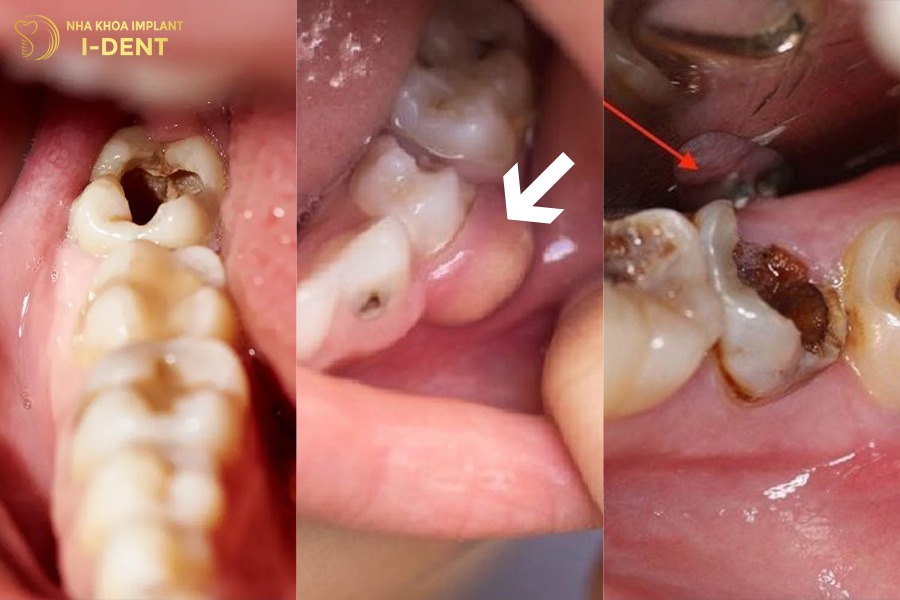

- Sâu răng: Răng số 6 mọc sớm (khoảng 6–8 tuổi) khi trẻ chưa biết cách chăm sóc răng miệng đúng nên dễ bị sâu. Khi sâu tiến triển nặng sẽ phá hủy men răng và ngà răng dẫn đến viêm tủy, áp xe hoặc gãy vỡ thân răng nên phải nhổ bỏ răng.

- Tai nạn hoặc chấn thương gãy, vỡ chân răng: Các va đập mạnh do té ngã, tai nạn hoặc thói quen cắn vật cứng có thể làm nứt, gãy thân hoặc chân răng. Trường hợp tổn thương quá sâu không thể phục hồi sẽ dẫn đến mất răng số 6 vĩnh viễn.

Nguyên nhân gây mất răng số 6 lâu năm.